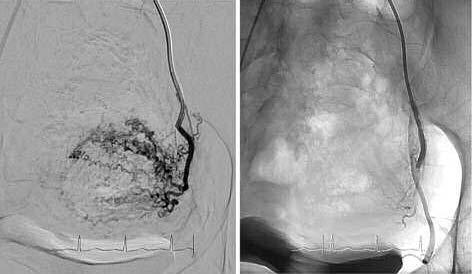

На момент госпитализации состояние пациентки было средней тяжести. Кожа и видимые слизистые чистые, несколько бледной окраски, тоны сердца ясные и ритмичные, дыхание везикулярное, артериальное давление 120/80 мм рт. ст., пульс 80 уд/мин. Живот мягкий, болезненный в нижних отделах, симптомы раздражения брюшины отрицательные. Печень и селезенка не увеличены. Симптом Пастернацкого отрицательный с обеих сторон. Осмотр в зеркалах: влагалище свободное, шейка матки цилиндрической формы, выделения обильные, зловонные, цвета мясных помоев с примесью гноя. При бимануальном исследовании: матка увеличена соответственно 15 нед беременности, бугристая, подвижная, умеренно болезненная. В общем анализе крови определялся лейкоцитоз (13,0¥109) с выраженным сдвигом лейкоформулы влево (палочек – 41, миелоцитов – 1), гемоглобин 86 г/л, фибриноген по Клаусу 6,8 г/л; D-димер 438 нг/мл, СОЭ 50 мм/ч, С-реактивный белок 85,7 мг/л, прокальцитонин 1,2 мкг/л. Бактериологическое исследование посевов крови и содержимого половых путей не позволило выявить возбудитель. При трансвагинальном ультразвуковом исследовании (УЗИ) матка – 135¥103¥119 см, в проекции матки определялось образование размерами 117¥81¥97 мм с интерстициально-субмукозным расположением, неоднородной структуры с наличием кистозных полостей и множественными линейными гиперэхогенными структурами, цервикальный канал расширен до 4 мм с изогиперэхогенным содержимым (рис. 1).

Рис. 1. Трансвагинальное УЗИ органов малого таза на момент поступления пациентки в стационар (по задней стенке визуализируется образование, расположенное интерстициально-субмукозно, неоднородной структуры).